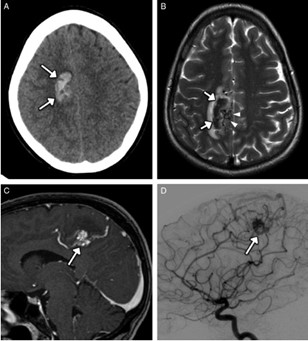

Los estudios de TC permiten evidenciar los accidentes cerebrovasculares (ACV) ocasionados por el abuso de la cocaína. Por caso, se localizó en la literatura imágenes que permiten ver el ACV isquémico agudo de la arteria cerebral media izquierda de un paciente. La TC sin contraste intravenoso visualiza la hipodensidad de la cabeza del caudado, del núcleo lenticular y de la ínsula izquierda. También se realizaron estudios de RM, que permiten observar la restricción del área isquémica en el territorio silviano(18) (ver Imagen 5).

Los consumidores habituales de cocaína suelen tener un pico de presión arterial sistólica elevada y un aumento de la frecuencia cardíaca tras el consumo, que los hace propensos a sufrir malformaciones arterovenosas. Al mismo tiempo, si esta sustancia se combina con etanol, las probabilidad de padecer una hemorragia subaracnoidea se incrementan. A propósito, se puede mencionar el caso de una paciente de 33 años de edad con síntomas de cefalea intensa y hemiparesia izquierda, en cuyo análisis de tóxicos de orina se detectó cocaína.(18)

En el caso que se viene reseñando, se realizó TC sin contraste para evidenciar eventuales daños isquémicos. En este estudio se localizó un hematoma intraparenquimatoso (ver Imagen 6). Este tipo de hematomas tiene un significativo riesgo para la persona, dado que puede avanzar hacia hemorragias con daño en la barrera hematoencefálica e incremento de la presión intracraneal, que puede ocasionar déficit neurológico e incluso la muerte.(17, 18)

En los casos de personas sin patología vascular subyacente, las hemorragias intraparenquimatosas se localizan con mayor frecuencia en los ganglios basales y el tálamo. Un caso como este se obtuvo en la literatura, correspondiente a una mujer de 23 años que sufrió una hemiplejía completa. Se le localizaron cantidades considerables de cocaína en el análisis de orina. La RM evidenció una isquemia en la rama MCA derecha con afectación de los ganglios basales(17) (ver Imagen 7).

Otro caso que conviene referir es el de una mujer de 19 años, quien acudió al servicio de guardia por dolor de cabeza agudo. Se le realizó una TC que mostró una hemorragia intraventricular con un posible componente parenquimatoso cerca de la pared del ventrículo derecho, a partir del abuso de cocaína en combinación con alcohol (ver Imagen 8). De igual modo, la angiografía evidenció una malformación arteriovenosa coroidea alimentada por la arteria coroidea lateral posterior(17) (ver Imagen 9).